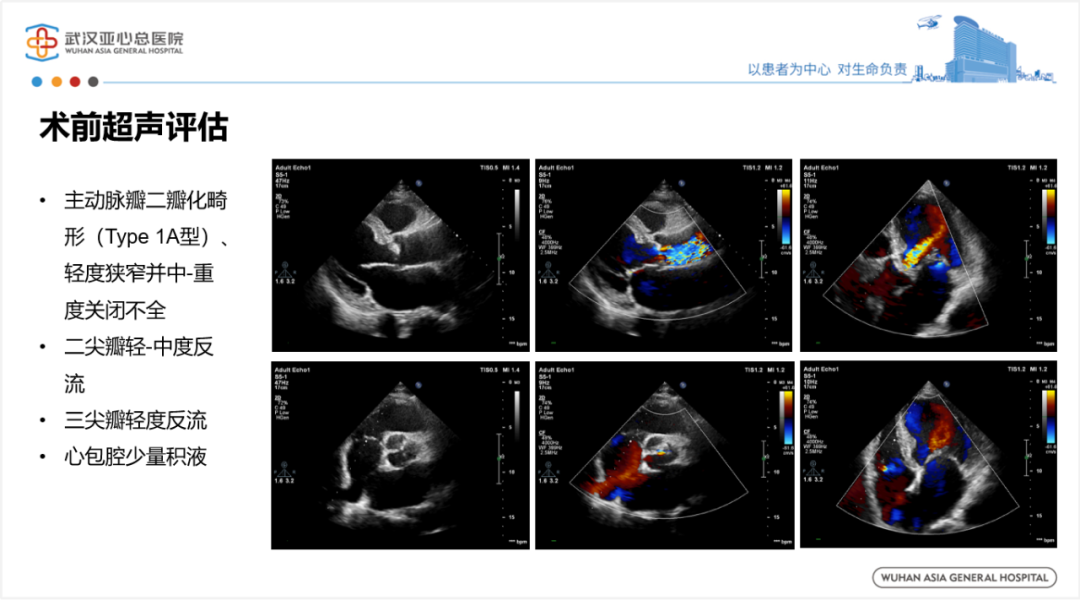

2.术前超声评估